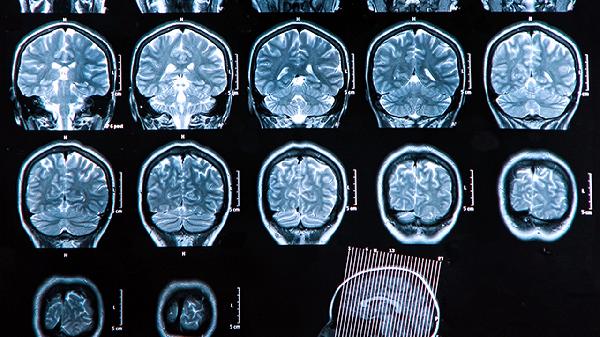

颅骨修复手术通常采用钛网或peek材料进行缺损修补,术后拆线时间与手术切口愈合速度密切相关。传统开颅手术切口较大,需分层缝合头皮各层组织,愈合时间相对较长。微创手术切口较小,组织损伤轻,愈合速度较快。术后医生会定期检查切口愈合情况,确认无红肿渗液等感染迹象后安排拆线。患者年龄、营养状况、基础疾病等因素也会影响愈合进程。